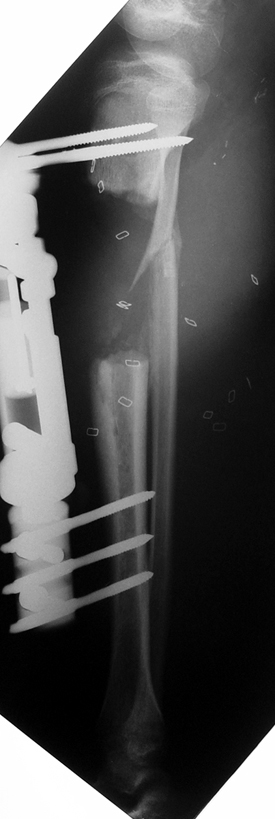

Case 3